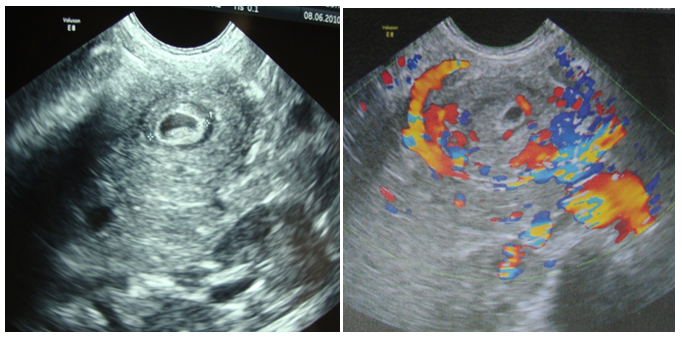

A two year old girl was presented in emergency for paroxystic abdominal pain without vomiting or other signs. The physical exam showed an epigastrium mass of 3cm which is round, tense, smooth and non tender beneath the umbilicus. Biologic exams were normal. Abdominal ultrasound with computer tomography revealed a cystic epigastric mass of 4.3cm with a wall that took contrast (Figure 3). Around this mass there was an ultrasound aspect of volvulus (Figure 4). A barium-meal examination demonstrated delayed gastric emptying through a narrowed pyloric antrum, which was distorted by a non communicating mass (Figure 5). At laparotomy, a cystic mass measuring approximately 4 × 3cm was identified anterior and lateral to the pyloric channel, sharing a common wall. The mass compressed the pyloric channel, resulting in partial gastric outlet obstruction. The duplication cyst did not communicate with the pyloric channel. Most of the cyst was excised, and the mucosa of the remnant cyst wall was cauterized. Histologic examination revealed gastric mucosa with a smooth muscle coat, which was consistent with a pyloric duplication cyst. No aberrant tissue was seen. The postoperative course was uneventful. The patient was asymptomatic 4years later.

Figure 3 Computer tomography: Cystic epigastric mass with a fine wall ( ☆ ) that took contrast.

Figure 4 Ultrasound aspect of volvulus around the mass.